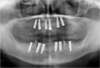

Programmation et mise en place des implants (6 implants maxillaires :haut et 6 mandibulaires : bas)

Radiographie implants en place